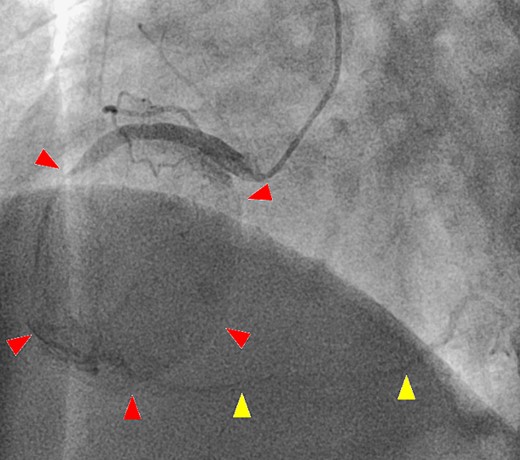

After a median sternotomy, the right gastroepiploic artery was harvested. Cardiopulmonary bypass was established with ascending aortic cannulation and bicaval drainage. The giant CAA was present at the right ventricle (Fig. 4A). The inflow and outflow coronary arteries surrounding the CAA were identified, and the heart was arrested with antegrade cardioplegia. Coronary artery bypass grafting (CABG) was performed (right gastroepiploic artery–RCA distal to the CAA), and the CAA was cut after ligating the inflow and outflow vessels. The inner area of the CAA was filled with a thrombus, and the thrombus was removed immediately. There was no ostium of the other vessels (Fig. 4B); thus, the CAA wall was resected and the remnant wall was sutured. The postoperative course was uneventful. Postoperative computed tomography showed shrinkage of the CAA and no contrast in it, and confirmed patency of the bypass graft. The histopathological findings of aneurysm wall revealed that it was the pseudoaneurysm.

Intraoperative image from the surgeon’s perspective. (A) There is a giant coronary artery aneurysm (arrow) on the right ventricle. (B) A view of the inside of the aneurysmal sac (arrow).